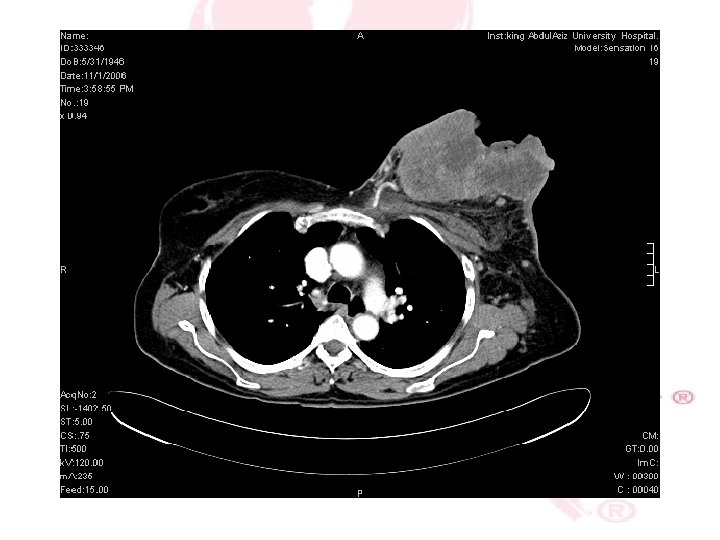

CT SCAN CHEST , ABDOMEN &PELVIS